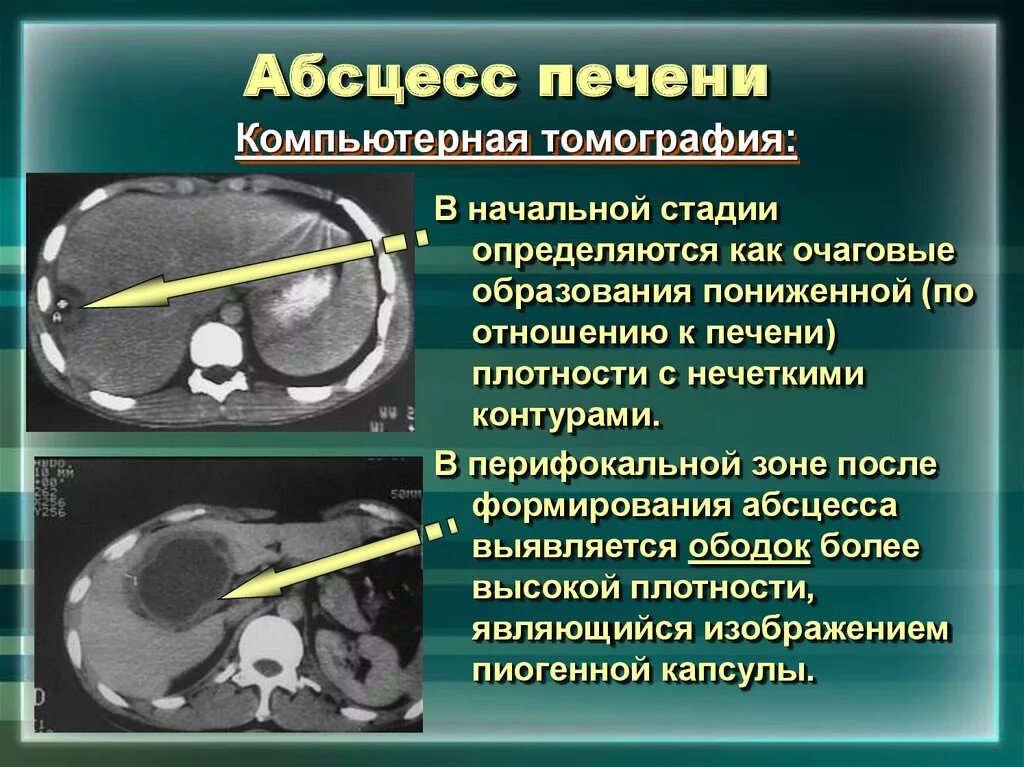

Онкология головного мозга. Раковые заболевания головного мозга. Амебиазный абсцесс печени. Солитарный абсцесс печени. Амебный абсцесс печени кт.

Амебиазный абсцесс печени. Солитарный абсцесс печени. Амебный абсцесс печени кт. Злокачественные опухоли щитовидной железы классификация. К злокачественным новообразованиям щитовидной железы относятся:. Доброкачественные щитовидной железы классификация. Доброкачественные новообразования щитовидной железы.